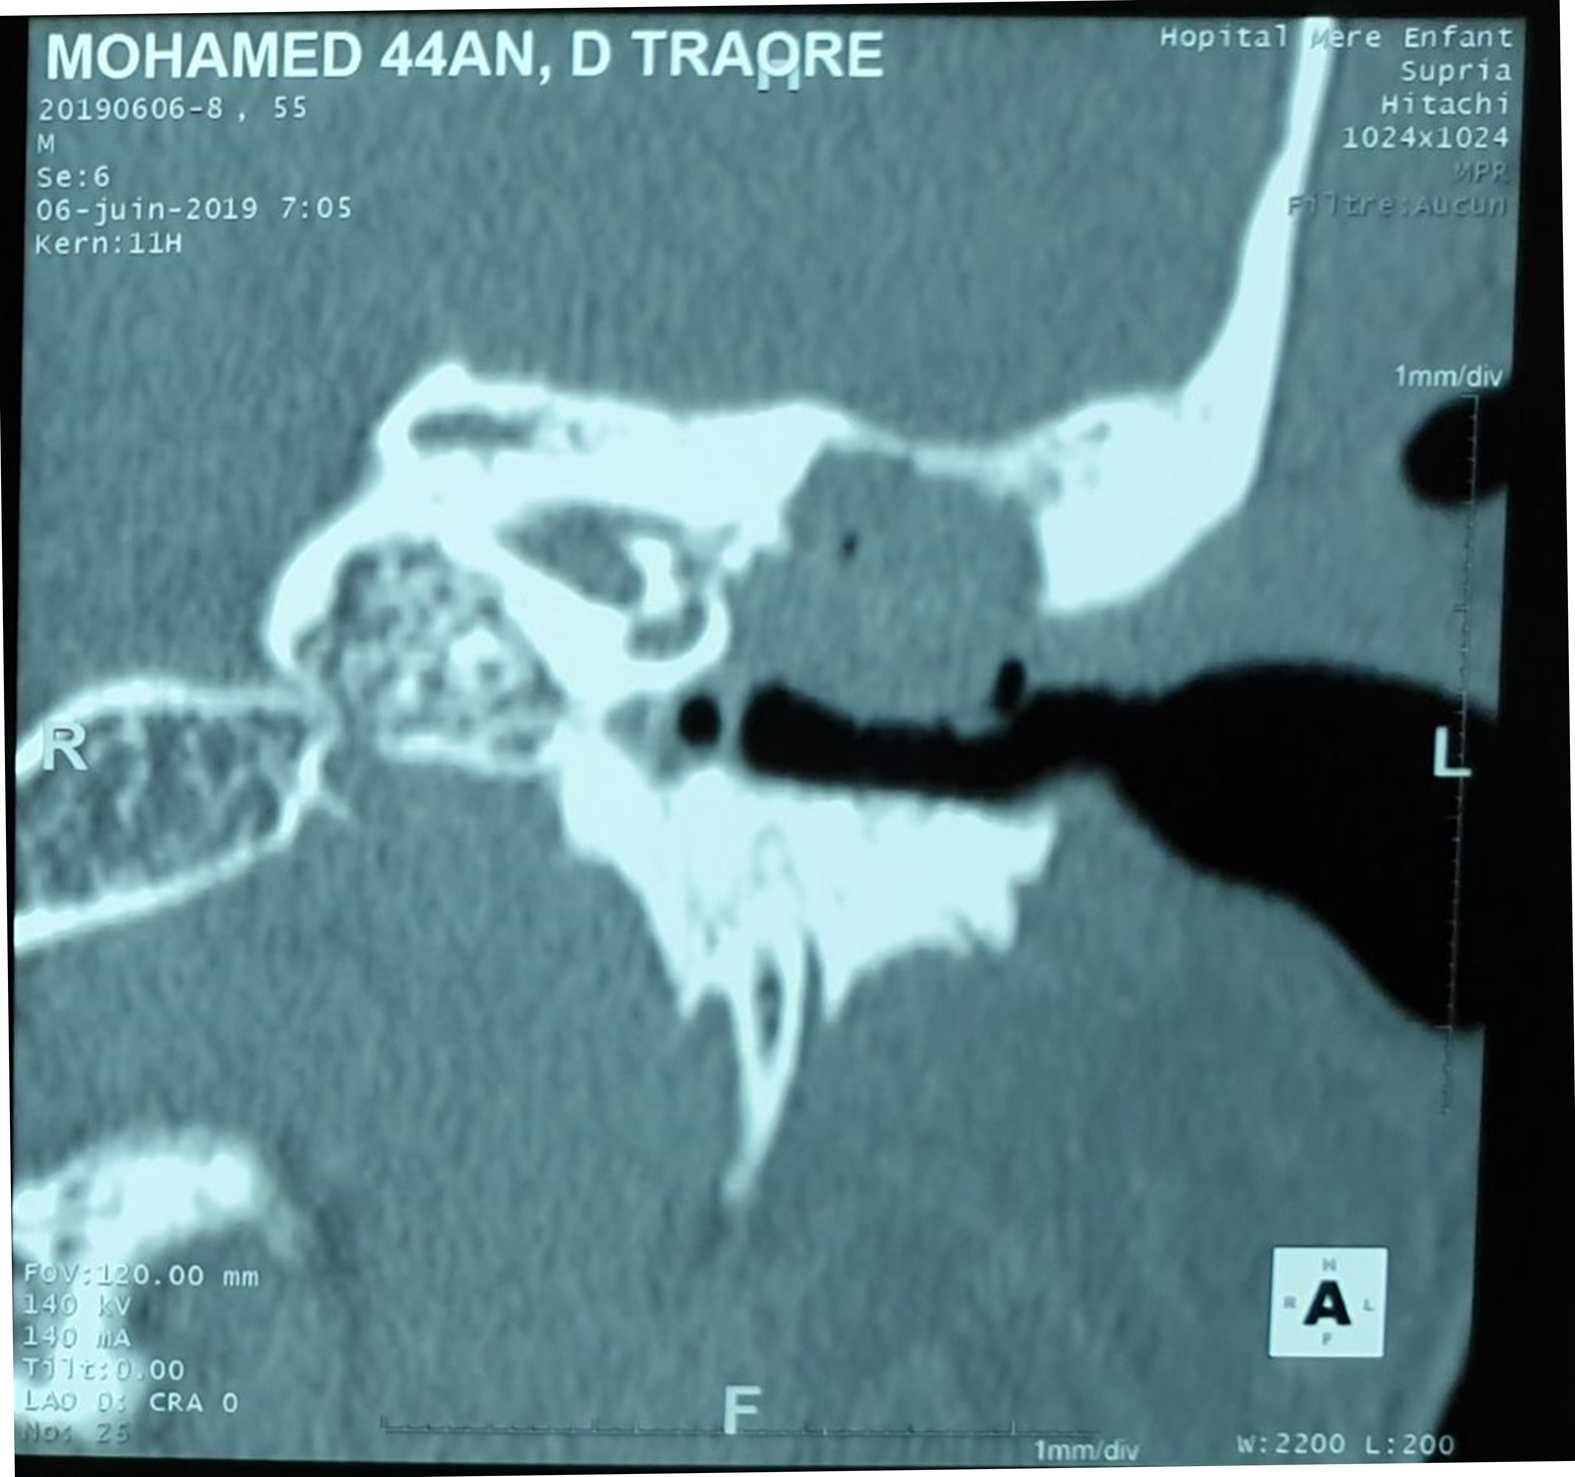

In total, we collected 34 files of patients admitted for cholesteatoma. This represented 9% of cases compared to all otological surgeries carried out during the same period, i.e. 362 cases. The 20 - 40 year old age group was the most represented with 65% (Table 1). The male gender was the most represented in 70.58%. ATCDS of recurrent otitis were the most represented with 75% of cases. The main functional signs were dominated by chronic fetid purulent otorrhea associated with hypoacusis in 94.6% of cases. One case of meningeal complication and three cases of cerebral empyema were reported. Clinically, a postero-superior and marginal tympanic perforation was observed in 53%, a retraction pocket in 5.9%, the sentinel polyp in 9%, and a non-marginal tympanic perforation in 32%. The left ear was the most affected in 67.64%. Conductive hearing loss accounted for 88.23% and mixed hearing loss was 11.77%. The average hearing loss of 40 - 70 dB was the most represented in 61.76% of cases and the average preoperative audiometric Rinne was 35 to 40 dB in 21 cases or 61.76% of cases. The CT of the rocks showed a total filling of the EAC with erosion of the wall of the cubicle and the tympanal bone in one case or 2.94%, a total filling of the middle ear with erosion of the wall of the cubicle and lysis of the ossicular chain in 50.00% of cases, total filling of the middle ear with lysis of the tegmen tympani and extradural empyema in 3 cases or 8.83% (Figure 1, Figure 2), in 2 cases extension was associated with lysis of the facial canal and also 2 cases of lysis of the mastoid cortex. In 6 cases the location was purely attical (Table 2).

Figure 1. Chronic right otomastitis, erosive suppurative with a small cerebellar extradural empyema.

4.2.2. CT of the Rocks

In our series, the CT of the rocks showed a total filling of the EAC with erosion of the wall of the cubicle and the tympanal bone in one case, i.e. 2.94%, a total filling of the middle ear with erosion of the wall of the ear. the cubicle and lysis of the ossicular chain in 50.00% of cases, total filling of the middle ear with lysis of the tegmen tympani and extradural empyema in 3 cases or 8.83%, in 2 cases the extension was associated with lysis of the facial canal and also 2 cases of lysis of the mastoid cortex. In 6 cases the location was purely attical. Our study is equivalent to those of the authors [3] [7]-[9]. This is explained by the fact that modern imaging currently occupies a preponderant place in the preoperative and postoperative management of ear cholesteatoma [5]. Preoperatively, performing a CT scan is systematically recommended, to clarify the extensions of the cholesteatoma, screen for possible complications, assess the anatomy of the tympanomastoid cavities (in particular the surgical risk variants) and compare the diagnosis. in the rare cases where the otoscopic examination was unable to resolve the problem [6] [10]. As part of the initial assessment of a cholesteatoma of the middle ear, non-enhanced CT is the examination of choice. MRI can sometimes be useful to complement CT data in certain limited indications [3] [11]. Postoperatively, monitoring of operated cholesteatoma has also greatly benefited from advances in modern imaging, with CT and sometimes MRI, making it possible to better identify the indications for surgical revision [3]. Complications, intratemporal and endocranial, can be indicative of cholesteatomatous otitis. These are the complications that make this potentially fatal pathology serious [12].